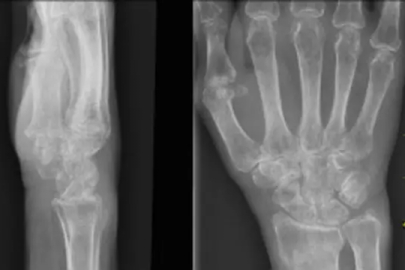

Nilüfer Belediyesi'nin düzenlediği "Kemik Erimesi ve Beslenme" başlıklı söyleşide konuşan Uzman Dr. Büşra Yeşil, osteoporozun (kemik erimesi) sessizce ilerleyen bir rahatsızlık olduğuna dikkat çekti. Dr. Yeşil, hastalığın önlenebilir yönlerine değinerek, beslenme ve egzersiz önerilerinde bulundu.

Erken menopoz, ailede kalça kırığı öyküsü, uzun süreli kortizon kullanımı ve tütün-alkol tüketiminin riskleri artırdığını vurgulayan Yeşil, hastalığın en ağır sonuçlarının kalça kırığı ve omurga çökmesi olduğunu ifade etti. Yapılan araştırmalara göre kalça kırığı yaşayan bireylerin iki yıl içinde yüzde 12 ile 20 arasında ölüm riski taşıdığını belirten Yeşil, bu durumun yaşam konforunu tamamen yok ederek, kişiyi başkasına bağımlı hale getirdiğini ekledi.